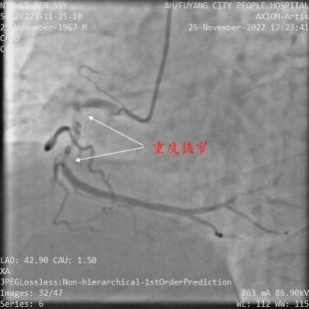

2月中旬,某患者,牛XX,男性,55岁,因冠心病、不稳定型心绞痛入住安徽省阜阳市人民医院,选择性冠状动脉造影(coronary angiography,CAG)示前降支7段和回旋支13段为CTO,右冠脉2段为重度狭窄,病变复杂,病情危重(图1)。当地医院反复尝试,历时约2小时前降支和回旋支均未能开通,遂建议患者3月后再次尝试PCI或选择CABG治疗。患者2月后慕名去武汉亚洲心脏病医院接受介入治疗,但尝试约2小时仍然未能开通前降支CTO(图2),建议患者接受CABG治疗。

图2 武汉亚洲心血管病医院手术资料